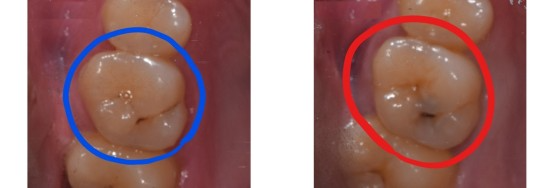

차이가 느껴지시나요?

파란색 치아도 관리가 잘되지 않는다면 빨간색 치아처럼 충치가 진행될 수 있습니다.

하지만 관리가 잘된다면 정지우식이 되고 치료할 필요가 없겠죠.

비교하기 편하게 같은 형태로 봐봅니다.

빨간색 치아의 충치는 충치 주변으로 멍이 든것처럼 검은색이 비쳐보입니다.

그리고 기구로 긁었을 때, 긁혀지는 진행중인 충치가 확인되어 치료를 하게 된 치아입니다.